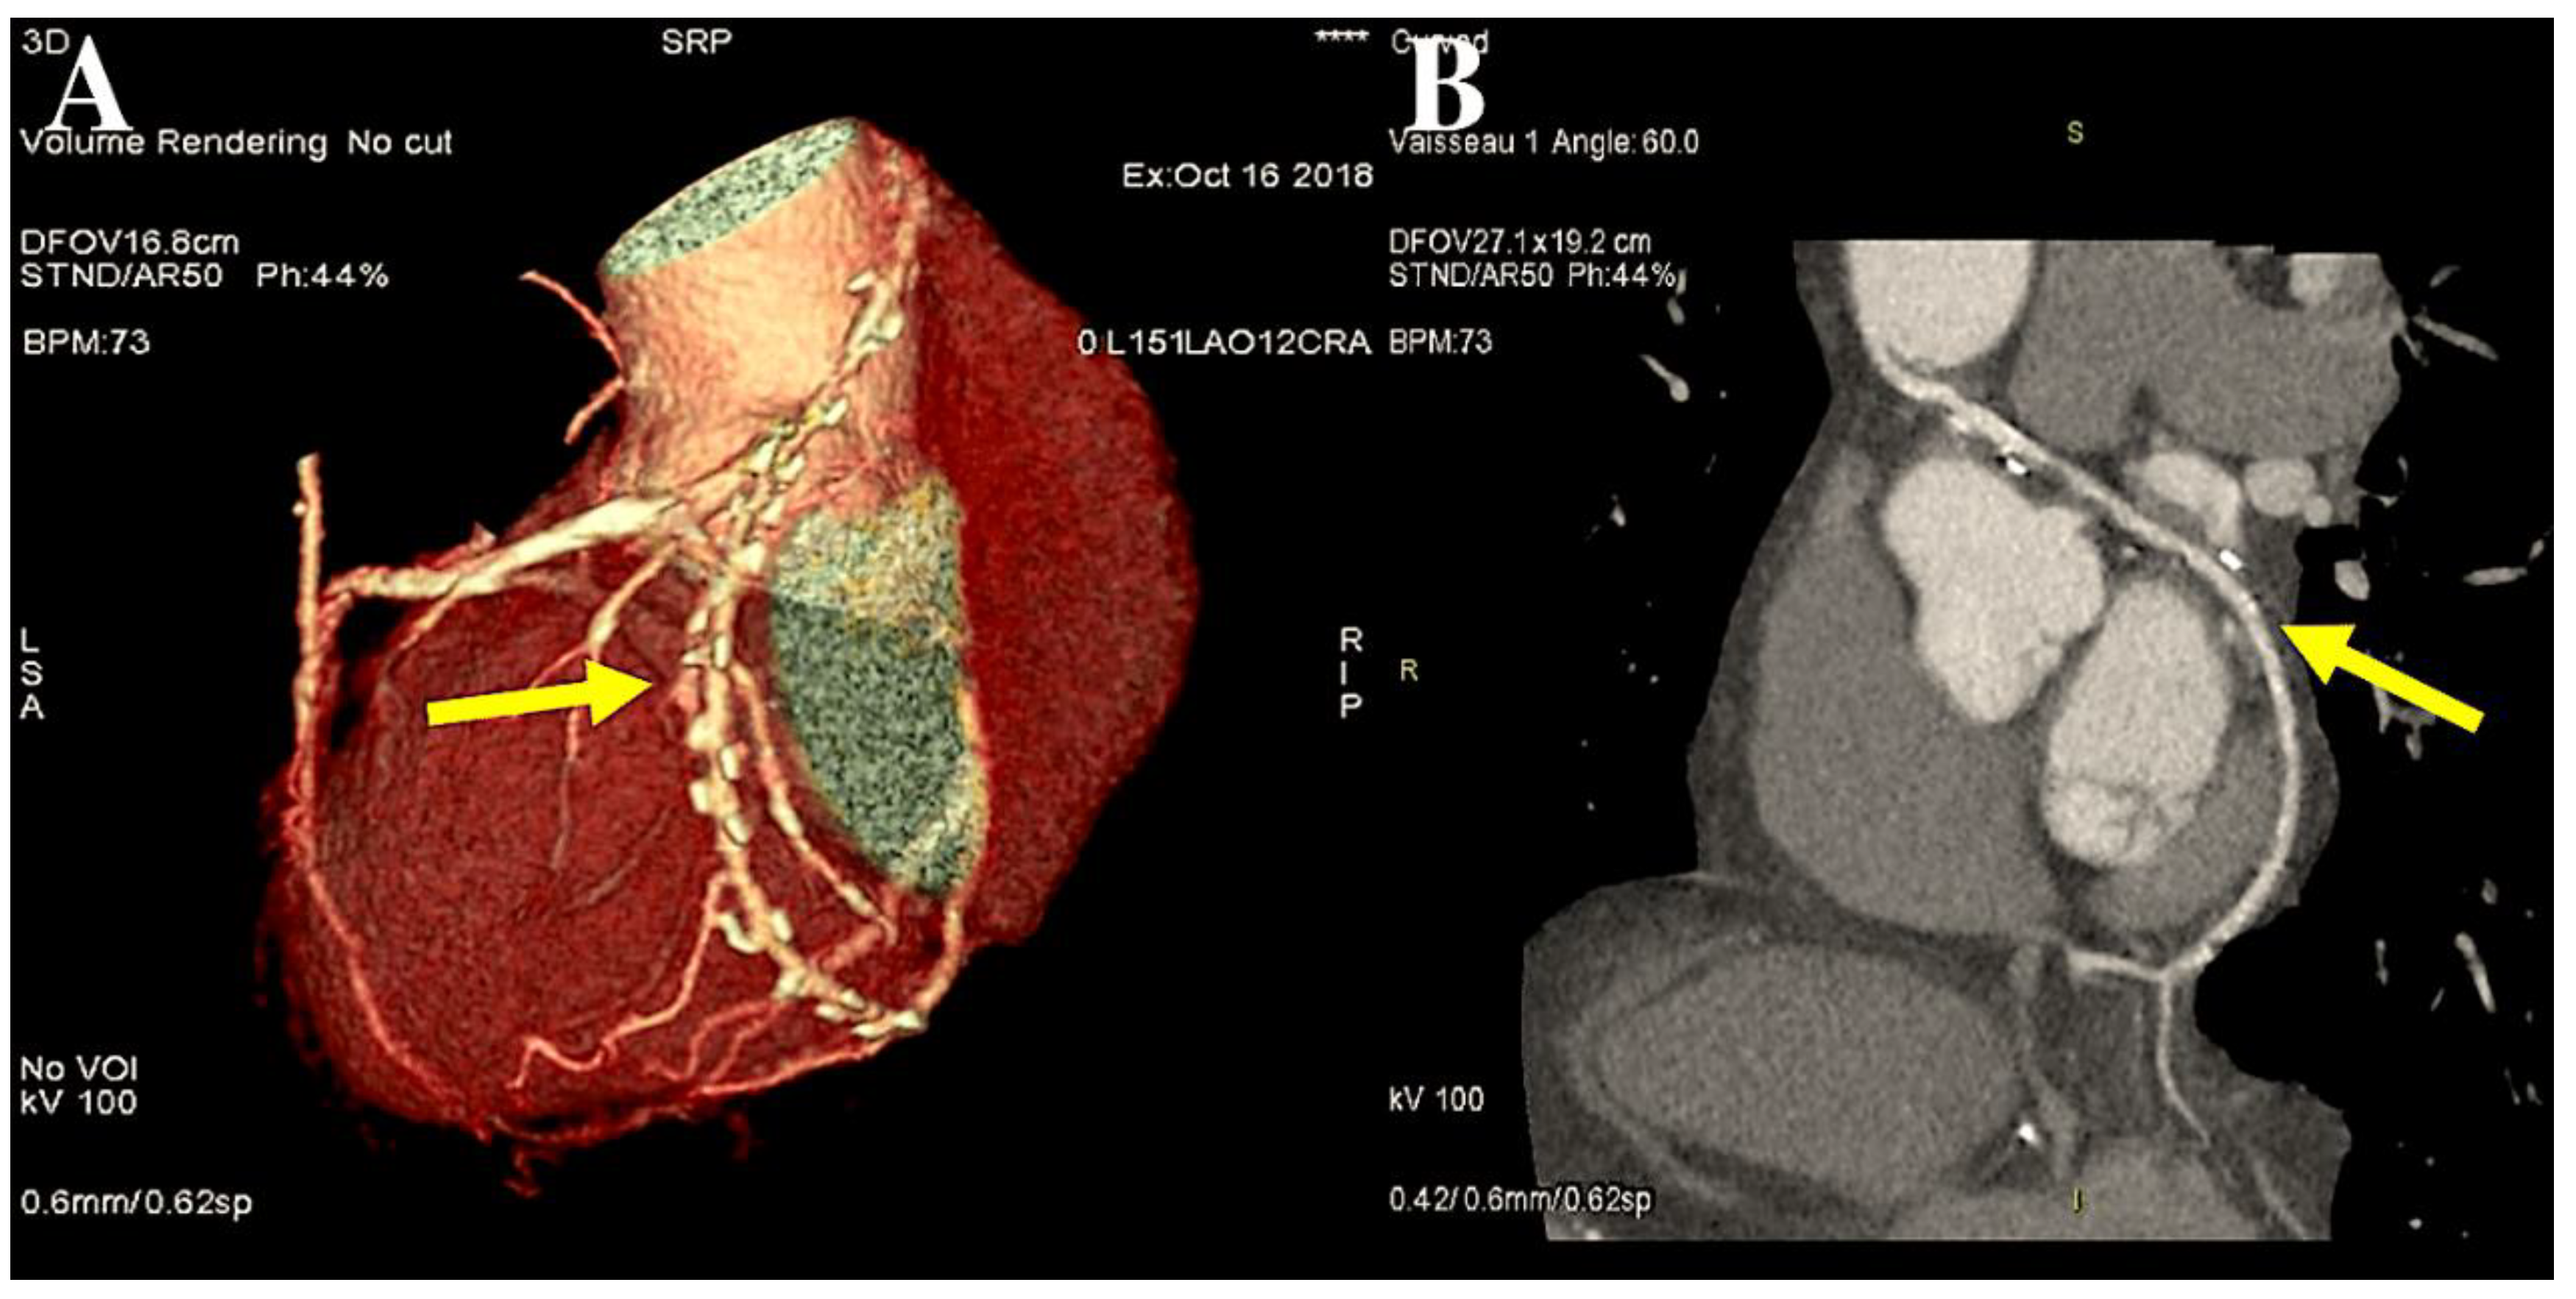

- Di Lazzaro D, Ragni T, Di Manici G, Bardelli G, Da Col U, Grasselli F, Antoniella A, Papa W, Crusco F, Giovagnoni A. Noninvasive midterm follow-up of radial artery bypass grafts with 16-slice computed tomography. Ann Thorac Surg 2006. 82:44-50. [CrossRef]

- Ropers D, Pohle FK, Kuettner A, Pflederer T, Anders K, Daniel WG, Bautz W, Baum U, Achenbach S. Diagnostic accuracy of noninvasive coronary angiography in patients after bypass surgery using 64-slice spiral computed tomography with 330-ms gantry rotation. Circulation. 2006;114:2334-41 . [CrossRef]

- Feuchtner GM, Schachner T, Bonatti J, Friedrich GJ, Soegner P, Klauser A, zur Nedden D. Diagnostic performance of 64-slice computed tomography in evaluation of coronary artery bypass grafts. Am J Roentgenol. 2007; 189:574-80. [CrossRef]

- Gaudino M, Prati F, Caradonna E, Trani C, Burzotta F, Schiavoni G, Glieca F, Possati G. Implantation in the coronary circulation induces morphofunctional transformation of radial grafts from muscular to elastomuscular. Circulation 2005;112 Suppl 9:I208–11 . [CrossRef]